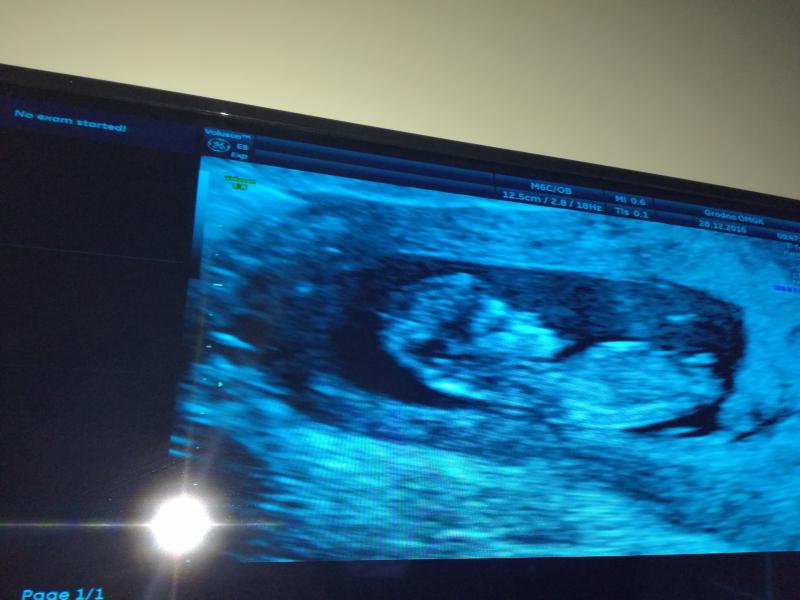

сегодня была НАША ПЕРВАЯ ВСТРЕЧА!Как это было трогательно,этот самый прекрасный звук сердцебиения !😅Нам подарок на годовщину свадьбы😍Папа счастлив как никогда,дочка в ожидании братика или сестрички!В общем не такой уж и плохой этот 2016🌸Всех с Наступающим,Всех Вам благ,здоровья Вашим близким,а беременяшкам Легких Родов😍😍😍😍😍